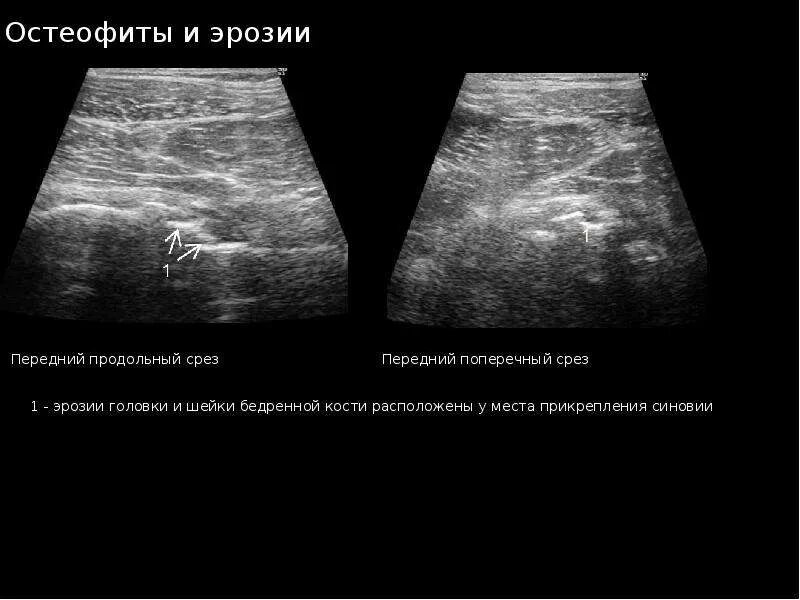

Делают ли узи тазобедренного сустава